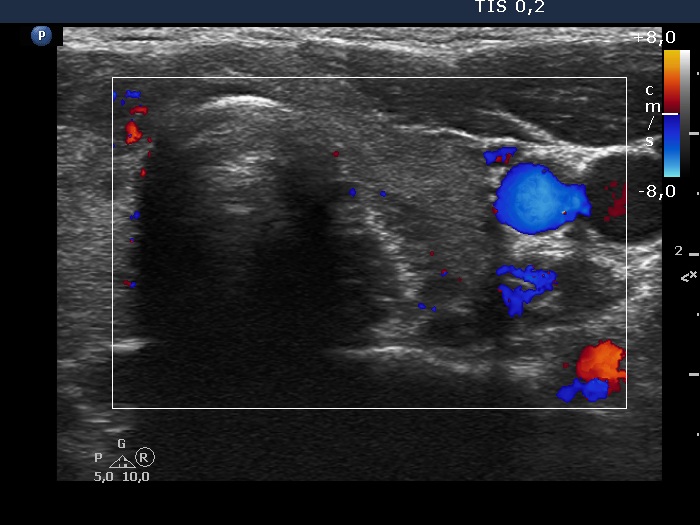

The shape of the nodule - case 2025 (ultrasonographic picture 7)

Left lobe, transverse scan, color Doppler mode. The vascularization is scanty.